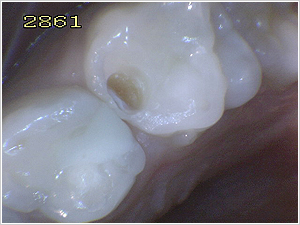

※下の3枚は差し上げた写真の例です。 |

これは治療前の乳歯です。歯と歯の間に虫歯があり、褐色が少し透けて見えます。 |

ある程度虫歯を削った時点です。底にまだ虫歯が残っています。 |